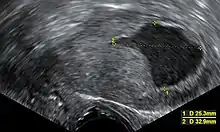

| Location | Mean (mm) | Range (mm) |

|---|---|---|

| Anterior wall | 23 | 17 - 25 |

| Posterior wall | 21 | 15 - 25 |

| Fundus | 20 | 15 - 22 |

| Isthmus | 10 | 8 - 22 |